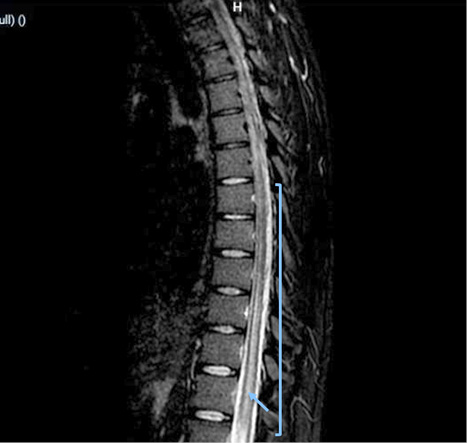

Due to early vesical incontinence, magnetic resonance imaging of the thoracolumbar spine was performed, which showed an alteration in the intensity of the spinal cord observed from the T2 level to the conus medullaris, which initiates in the anterior horns and then generalizes throughout the circumference of the spinal cord with significant thickening. These findings were consistent with longitudinally extensive transverse inflammatory myelopathy (Figure 1, 2, and 3).

Figure 1. MIR Sequence STIR: alteration in the intensity of the spinal cord observed from the T2 level to the conus medullaris, that initiates in the anterior horns and then generalizes throughout the circumference of the spinal cord with significant thickening of it